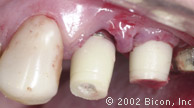

3. | 缺牙区牙槽嵴的唇侧观。 |